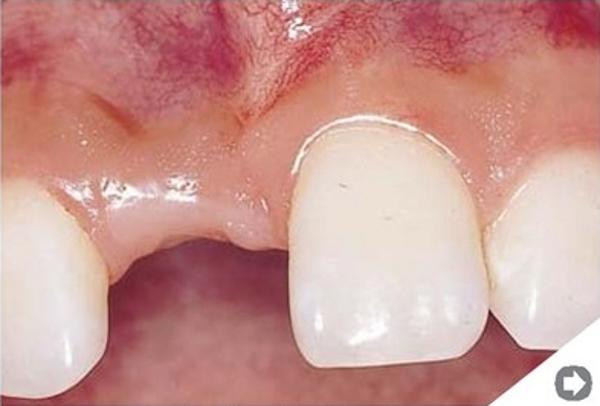

Przeszczep kości. W niektórych sytuacjach jest to jedyna skuteczna metoda odbudowy zanikłej kości. Zabieg polega na pobraniu fragmentu tkanki kostnej z innego miejsca jamy ustnej (albo przy większych przeszczepach z biodra) i następnym umocowaniu go w miejscu odbudowywanym. W ciągu kilku miesięcy następuje wgojenie się przeszczepu -€“ zamienia się on w pełnowartościową kość.